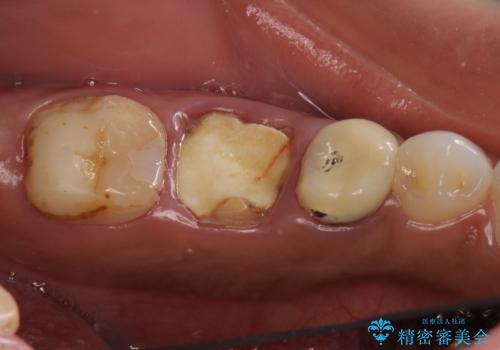

虫歯を放置したため、左下奥歯の上下の歯の隙間が全くなく入れ歯もインプラントも難しい状態でした。

左下6番は残根状態だったため、やむなく抜歯を行い、⑤6⑦ブリッジとしました。

歯周外科手術を併用し、骨の高さを調整して歯の高さをしっかり出す手術(クラウンレングスニング)も行いました。

また、左下を含めて全体的な虫歯治療も行いました。